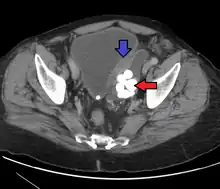

Urothelial carcinoma, previously called transitional cell carcinoma, is a type of cancer that can occur anywhere along the urinary tract.[7][8] This includes the kidneys, ureters, bladder, prostate, and urethra.[7][9] Symptoms may include blood in the urine, back pain, weight loss, or pain with urination.[1]

Risk factors include smoking, aromatic amines, arsenic, aristolochic acid, Schistosoma haematobium, and genetic disorders such as Lynch syndrome.[3][4][2] They develop from the transitional epithelium.[3] The diagnosis is generally confirmed by cystoscopy and biopsy.[5]